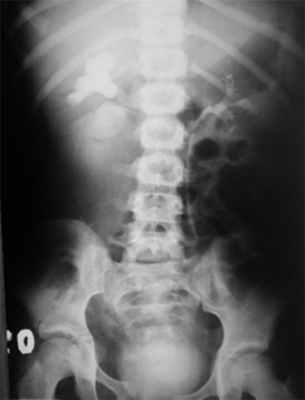

Дренажная система, установленная в забрюшинном пространстве, требовала ревизии в связи с отсутствием тенденции к разрешению урогематомы. Экскреторная урография, проведенная в этот период, показала, что правая почка функционирует, накопление и экскреция контрастного препарата происходят своевременно, но в области лоханочно-мочеточникового перехода есть зона непроходимости с полным отсутствием контрастирования правого мочеточника и экстравазацией мочи (рис. 2). Рис. 2. Экстравазация контрастного вещества с облитерацией пиелоуретерального перехода.